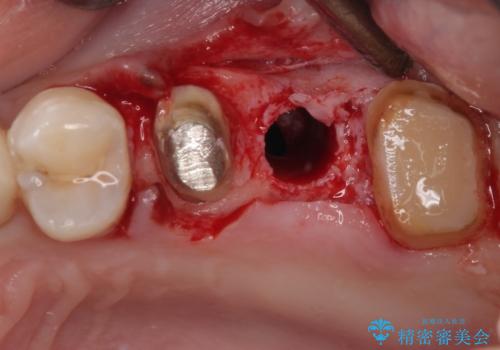

インプラントが必要となった奥歯は、インプラントが埋入できないほど隣の歯の根尖病変が非常に大きかったため、根管治療を行ったうえで半年ほど待ち、骨が再生したことを確認してからインプラントを埋入しました。期間は長くかかりましたが、大変良い仕上がりとなりました。